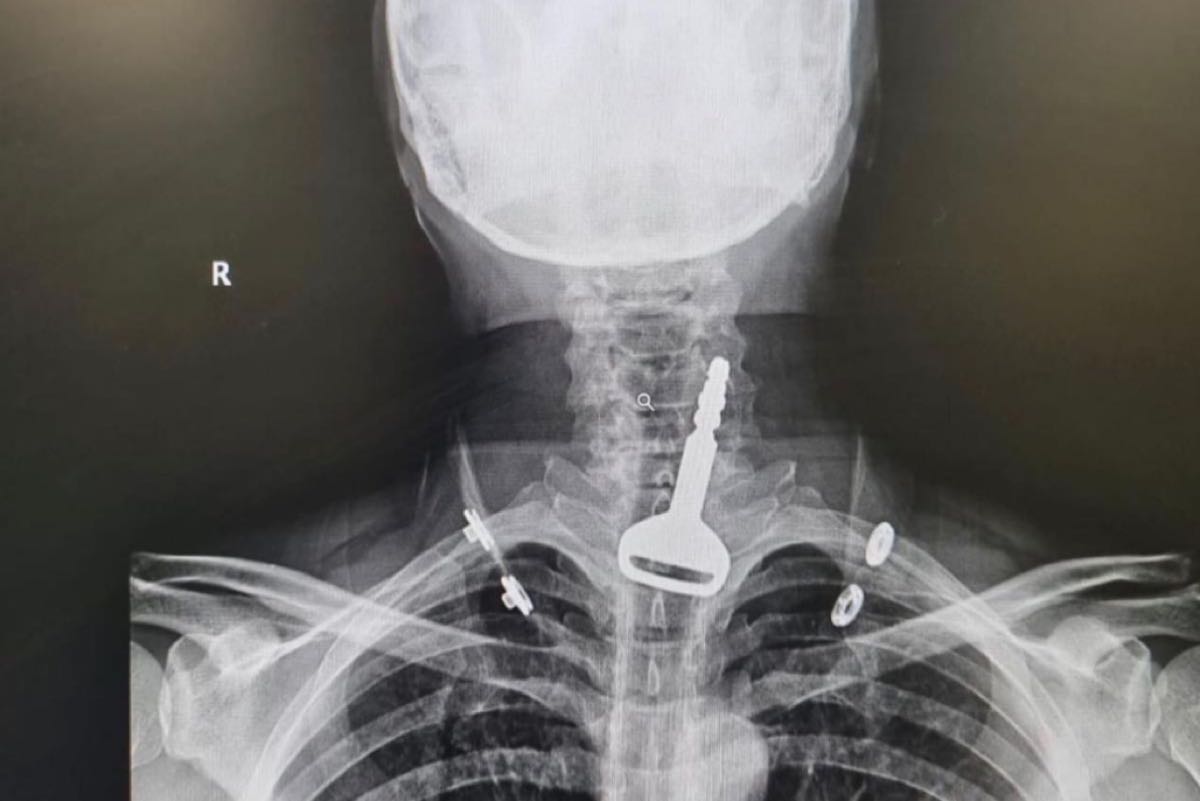

وأكدت وزارة الصحة أن الفرق الطبية تمكنت من إنقاذ حياة مريض يبلغ من العمر 49 عاما وصل لقسم الطوارئ وهو يعاني من انسداد بمجرى التنفس، حيث اتضح بعد إجراء الفحص السريري والأشعة وجود مفتاح سيارة عالق في القصبة الهوائية.

وأوضحت أن المريض الذي اعترف للأطباء بأنه كان يلهو بالمفتاح في فمه، ابتلعه عن طريق الخطأ، ما تسبب له في حالة اختناق جزئي، تطلبت التدخل الجراحي عن طريق المنظار لاستخراج الجسم المعدني العالق.